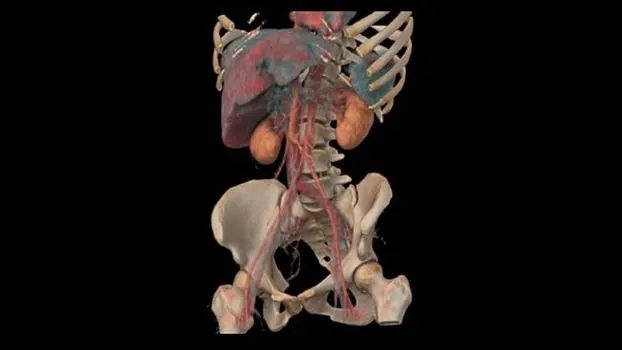

Клинические изображения

Клиническая эффективность

В КТ-исследованиях больше всего времени уходит не на само сканирование, а на подготовку пациента, реконструкцию изображений и создание заключительного отчета. С Revolution Ascend вы можете легко размещать пациентов с высоким ИМТ на столе и эффективно проводить интервенционные процедуры и любые другие исследования нажатием всего лишь двух кнопок.

Технология TrueFidelity

Revolution Ascend поддерживает технологию TrueFidelity**, которая реконструирует изображения с помощью алгоритмов глубокого обучения. Она обеспечивает глубокую детализацию, естественную текстуру, высокую контрастность и четкость изображений. TrueFidelity генерирует изображения с помощью алгоритмов искусственного интеллекта. Это позволяет, с одной стороны, использовать низкую лучевую нагрузку, как при итеративной реконструкции, а с другой стороны, получать изображения, не уступающие по качеству методу фильтрованных обратных проекций.